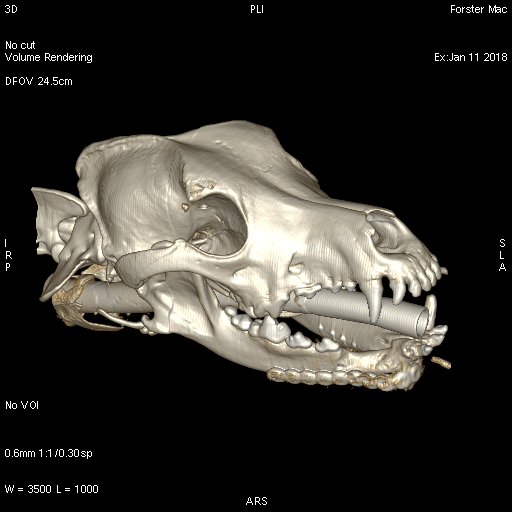

Mac was referred to the dentistry and oral surgery service at Eastcott Referrals. A high resolution computed tomography scan was performed of Mac’s jaw with a GE Lightspeed Four Slice CT Scanner in order to localise the tumour and define his margins. A 3D model was printed for planning of the surgery and preoperative plate contouring.

Fig. 4: Right lateral view of a three-dimensional reconstruction of a CT scan of the skull of a dog showing new bone formation and a complete bridge between the ends of the bone resection after a rostral segmental mandibulectomy.

A 3D printer was used to print a 3D model for the planning of this surgery and preoperative plate contouring. We find 3D printing for surgery pre-planning increasingly useful and have recently invested in our own 3D printer.